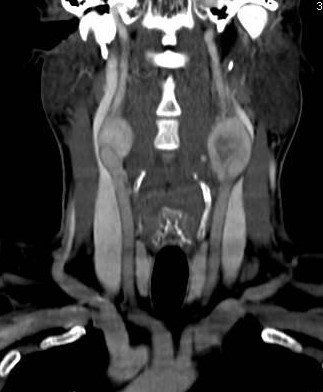

Masculino, 42 anos, Lesões expansivas nas bifurcações carotídeas.

Paraganglioma Carotídeo.

Os paragangliomas (tumores glômicos, glomus) são lesões originarias das células parangaglionicas da crista neural. São tumores pouco frequentes, benignos, de crescimento lento e extremamente vascularizamos. Suas principais localizações no espaço carotídeo são: na bifurcação carotídea, em torno do gânglio do nervo vago, junto a base do crânio, no bulbo jugular e comprometendo simultaneamente a orelha média e bulbo jugular.

Sua incidência costuma ser entre 40 e 50 anos e tem uma predileção pelo sexo feminino. São o tipo mais comum de paraganglioma (60-70%) e 10% dos casos são bilaterais.

• TC: Lesão de partes moles mal delimitada e ricamente vascularizara, com destruição permeativa das estruturas ósseas adjacentes, apresentando realce intenso no exame contrastado.

• RM: Sinal intermediário nas sequências ponderadas em T1 e hipersinal nas imagens ponderadas em T2, observando-se frequentemente imagens serpinginosas de ausência de sinal dentro da lesão em todas as sequências de imagem, característica da presença de vasos dominantes, associados a focos hemorrágicos, intratumoral, representados por focos de alto sinal (aspecto de sal e pimenta - identificação de vasos calibrosos no interior do tumor). O uso do contraste paramagnético evidencia sua hipervascularização.